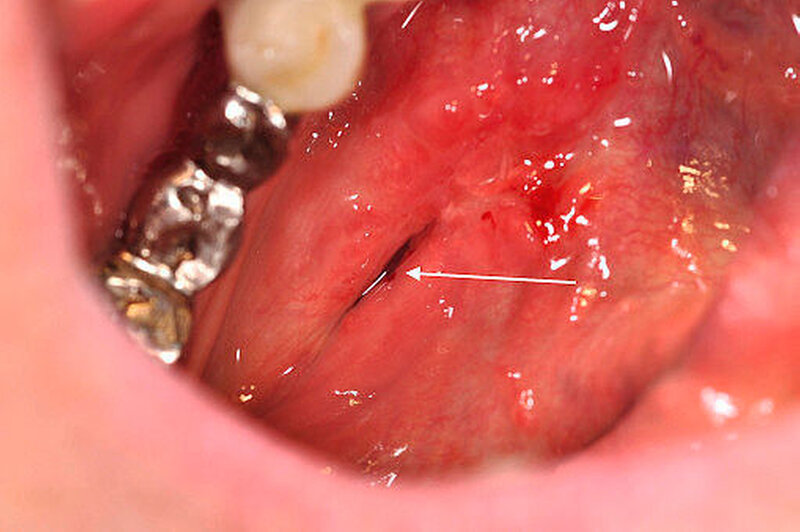

Im Januar 2016 stellte sich eine 71-jährige Patientin in der Klinik und Poliklinik für Mund,- Kiefer- und Plastische Gesichtschirurgie der Universitätsmedizin Rostock nach Überweisung mit Verdacht auf einen submandibulär rechts lokalisierten Speichelstein vor, der im Rahmen der Routineuntersuchung als Zufallsbefund detektiert wurde (Abbildung 1).

Aufgrund des ausgeprägten Lokalbefunds (Abbildung 2) konnte die Verdachtsdiagnose klinisch durch die bimanuelle Palpation des Mundbodens bestätigt werden. Die Bildgebung mittels Sonografie komplettierte das diagnostische Procedere (Abbildung 3). Nebenbefundlich nahm die Patientin aufgrund von anamnestisch rezidivierenden, tiefen Beinvenenthrombosen Rivaroxaban (Xarelto®, 20 mg, 1–0–0) zur Antikoagulation ein.